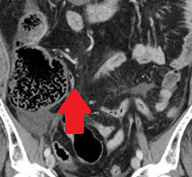

CT κοιλίας. Κόκκινο βέλος — Τυφλίτιδα. Σημαντική πάχυνση τοιχώματος τυφλού (Ευγενική παραχώρηση Dr. V. Penopoulos)